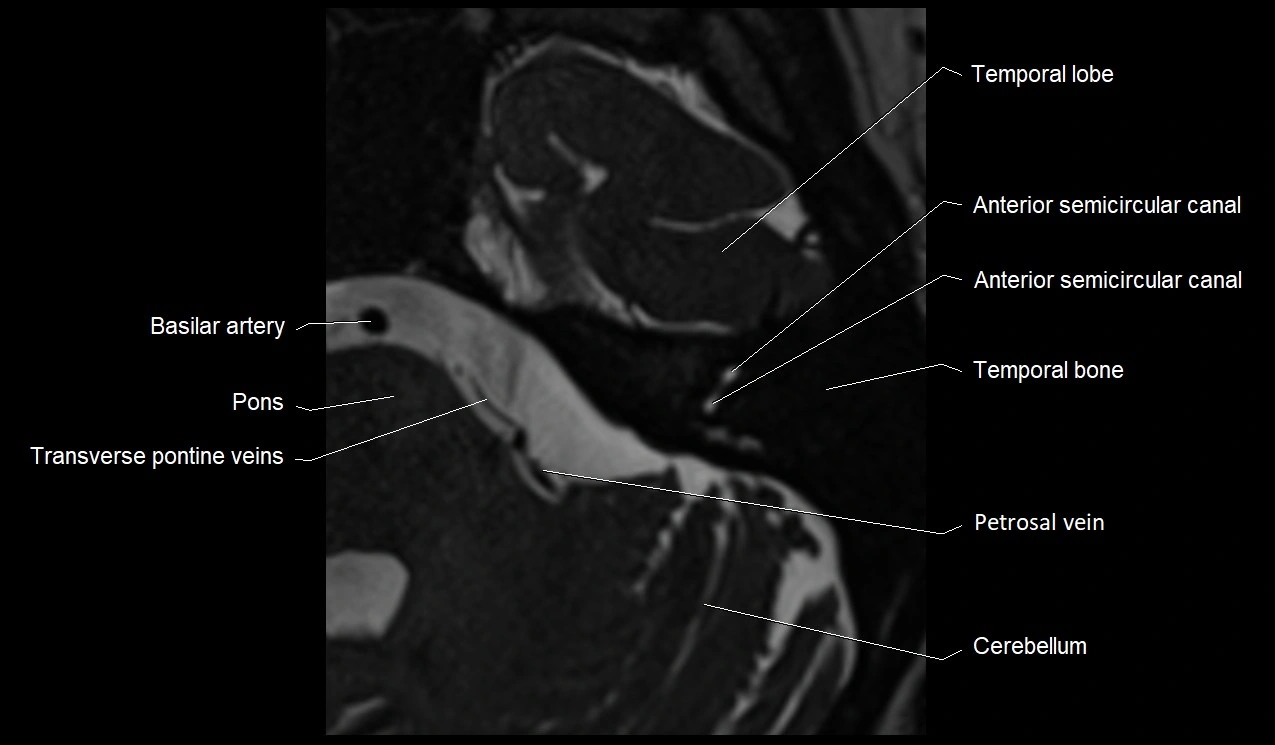

MRI Appearance

• The abducens nerve is a small, thin, linear structure

• Best visualized on high-resolution T2-weighted 3D MRI sequences (e.g., FIESTA or CISS)

• Seen as a hypointense (dark) line running from the brainstem at the pontomedullary junction, traversing the prepontine cistern, and entering Dorello’s canal under the petrosphenoidal ligament, then into the cavernous sinus, and finally the orbit

• May be challenging to visualize in standard MRI due to its small size

• Pathology may be inferred by absence, displacement, or enhancement of the nerve